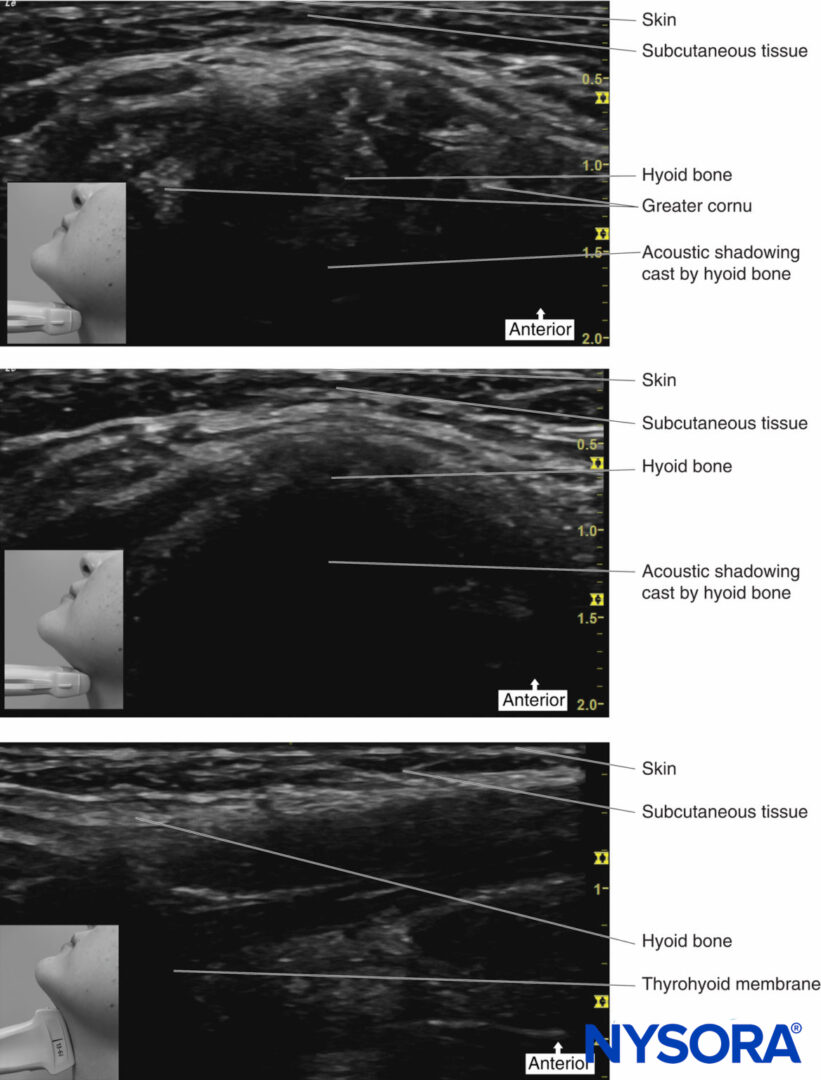

Ultrasound can be used to help increase the success rate of performing some of the blocks described (Table 2). Ultrasound can increase the accuracy of the deposition of local anesthetic around the greater cornu of the hyoid bone for the superior laryngeal nerve block and can be used to identify the cricothyroid membrane for translaryngeal blocks.

Sometimes, it can be difficult to identify the landmarks (eg, in obese patients) when trying to perform this block. Ultrasound can therefore be used to facilitate the deposition of local anesthetic to the correct place. The hyoid bone can be visualized on ultrasound (Figure 13), and an in-plane technique can be used to deposit local anesthetic around the surface of the greater cornu of the hyoid bone to achieve the block.

FIGURE 13. Ultrasound images of hyoid bone.

Place the transducer probe in the sagittal plane to identify the greater cornu of the hyoid bone; the transducer is then rotated transversely to identify the superior lateral aspect of the thyrohyoid membrane. The superior laryngeal nerve can be seen superficial to the thyrohyoid membrane when the medial aspect of the probe is rotated cephalad. The internal branch of the superior laryngeal nerve runs along with the superior laryngeal artery, just below the greater cornu of the hyoid bone.

An alternative approach is to identify the hyoid bone, which appears as a hyperechoic curved bright structure on ultrasound in the midline. If the probe is moved laterally, the greater cornu of the hyoid bone can be seen as a bright structure medial to the superior laryngeal artery. The internal branch of the superior laryngeal nerve runs with the superior laryngeal artery just below the level of the greater cornu of the hyoid bone. Using an in-plane technique, a needle is passed perpendicular to the skin, aiming just below the greater cornu of the hyoid bone.

Then, 1–2 mL of local anesthetic can be injected here after negative aspiration (Figure 14).

This technique has been shown to have a success rate of over 90%. Failure is thought to be due to variations in the anatomical position of the superior laryngeal nerve in relation to the hyoid bone.